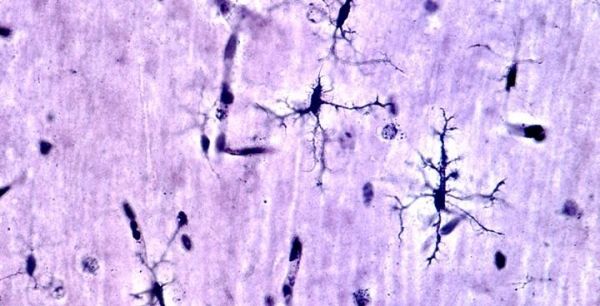

Image: Microglia are specialized cells that work to clear away debris in the brain and perform other essential duties. These cells typically become dysregulated in Alzheimer's disease (AD), leading to inflammation and neuronal death. Intriguingly, the beneficial effects of lifelong choline supplementation reduce the activation of microglia in mice bred to develop AD-like symptoms. The choline-rich diet is shown to improve cognitive function. (Credit: Arizona State University)